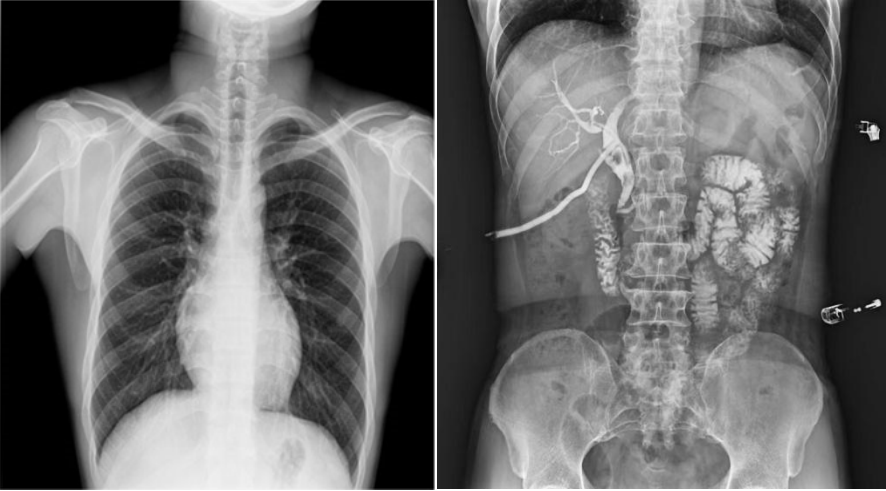

高幀動(dòng)態(tài)平板,快速獲得高清影像。線性探測(cè)平面,圖像無畸變、無失真;17×17英寸超大視野,透視幅面大,一幅畫面即可覆蓋成年人的全胸全腹;30幀/s采集幀速,畫面流暢無卡頓;1800W高清像素點(diǎn)片,影像質(zhì)量攀升新高度;并且能夠在毫秒級(jí)時(shí)間內(nèi)進(jìn)行動(dòng)靜態(tài)影像切換,實(shí)時(shí)點(diǎn)片,快速捕捉病灶部位。